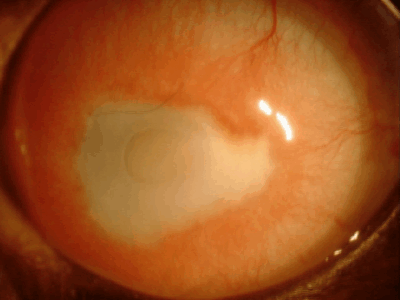

強膜充血

結膜の下の強膜血管が怒張し赤く見えます。結膜充血よりもやや太い血管が浮きでできます。原因としては、眼内の炎症(ぶどう膜炎)、緑内障などでみられます。